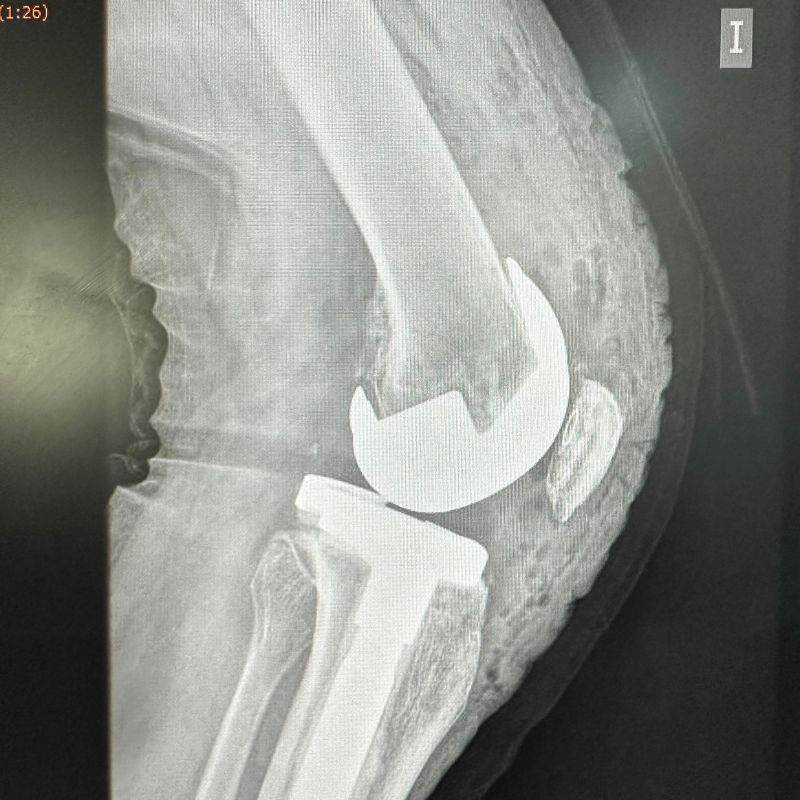

- Prótesis Total de Rodilla.

- Retiro de Prótesis de Rodilla dolorosa o fallida.

- Prótesis de Revisión de Rodilla.